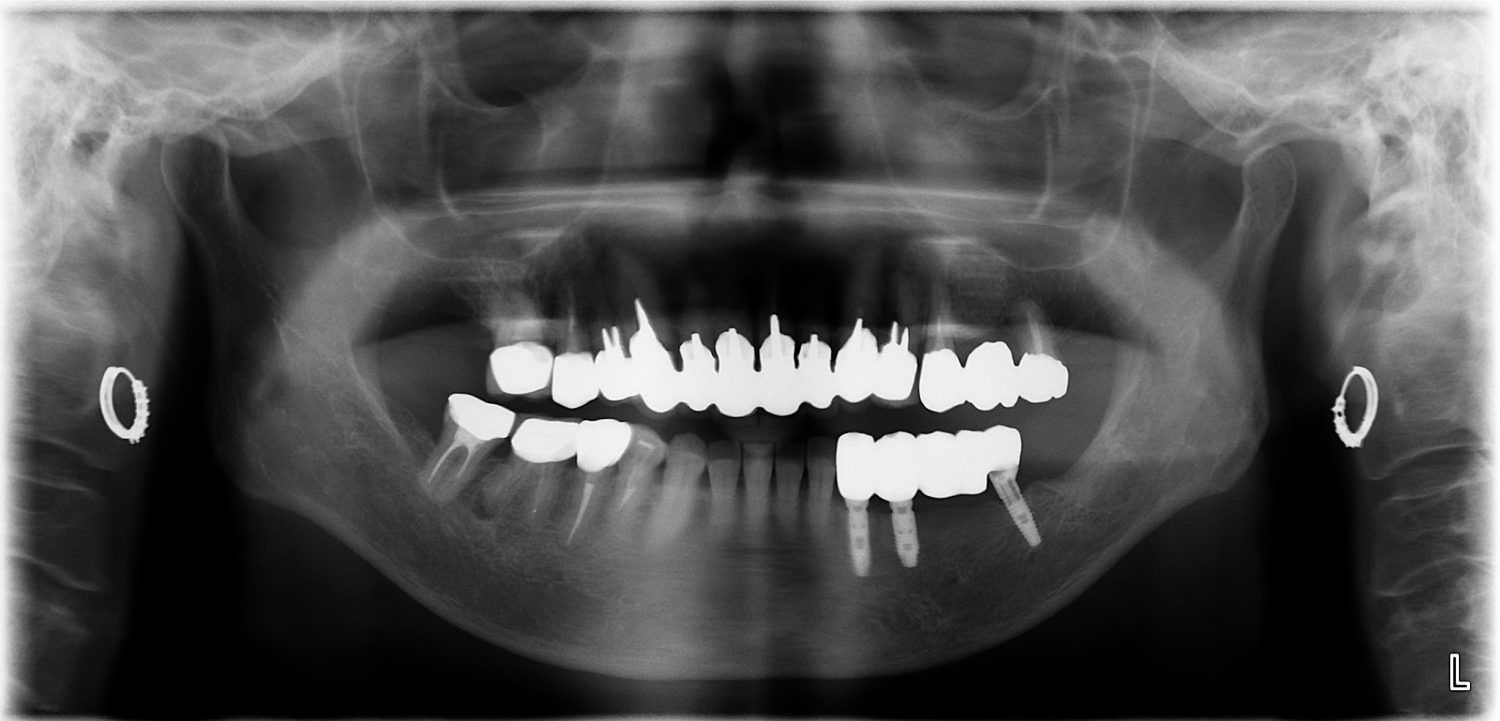

インプラント治療の症例紹介④

Before

After

主訴

義歯による疼痛

治療内容

下顎舌側に骨隆起があり義歯困難な状態。保存不可能な歯の抜歯を行い、インプラントを埋入し咬合再構成を行った。

治療費

2,851,200円(税込)

治療期間

29ヶ月

通院回数

26回

想定されたリスク

※咬合力の強い方なので、予防的にマウスピースの装着が必要。インプラント周囲炎の恐れがありました。

濱 仁隆先生

浜歯科

歯の欠損の対合歯の挺出等を修正し咬合平面を揃え咬合再構成を行った症例。